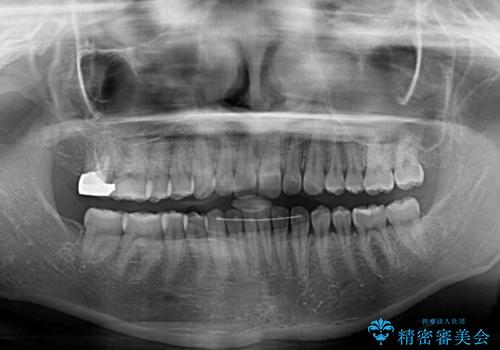

下顎前歯のデコボコが集中しており、奥歯の咬み合わせは、上顎に対して下顎が前方位にある状態でした。下顎の歯列を後方へ移動させる治療はインビザラインの得意とするところですので、1年程度で無事に治療を終えることができました。